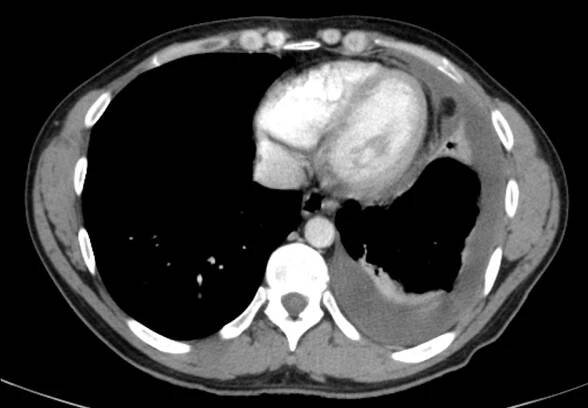

CT

Fluidothorax (fluidotorax) znamená přítomnost tekutiny v pleurálním prostoru, tj. v prostoru okolo plíce. Může být jednostranný nebo oboustranný a může mít celou řadu příčin. Je-li fluidothorax tvořen krví, hovoříme o hemothoraxu, a je-li…

Fluidothorax, pleurální výpotek, pohrudniční výpotek (laicky "voda na plicích") je lékařský termín, označující patologické nahromadění tekutiny v prostoru kolem plíce v tzv. pleurální dutině mezi pohrudnicí (parietální pleura) a poplicnicí (viscerální pleura). Fluidothorax je obecný název, který se dále konkretizuje dle zjištěného složení tekutiny. Obdobný stav je… Wikipedie